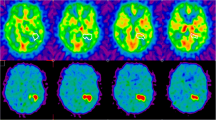

Many in vivo studies focused on the correlation of different methods for hypoxia detection in order to move from invasive to non-invasive ones. One study compared FMISO uptake in rodent tumour xenograft models with robotic-guided multiple pO2 measurement via electrodes and found a high non-concordance in some individual data pairs, possibly explained by partially necrotic, i.e. anoxic, subvolumes that do not take up the tracer (Chang et al. 2009). Numerous studies have shown a reasonably good correlation between hypoxic subvolumes as detected by pimonidazole immunohistochemistry and FMISO and FAZA uptake by autoradiography and/or microPET, under varying levels of oxygenation or artificially induced clamp hypoxia (Troost et al. 2008; Busk et al. 2008, 2009, 2013; Troost et al. 2006). Figure 3 depicts examples of pimonidazole-stained and FMISO-autoradiographed xenografts under different oxygen conditions.

Pseudo-coloured grey-value pimonidazole images (top row), images after segmentation of the pimonidazole signal (middle row), and FMISO autoradiography images (bottom row) of head and neck squamous cell carcinoma (SCCNij3) and glioblastoma (E106) xenograft tumour lines for control tumours, after carbogen breathing and clamping. Figure taken with kind permission from (Troost et al. 2006)